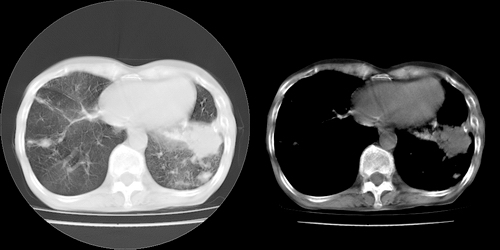

以下是引用lihuuuu在2006-7-18 18:16:00的发言:[br]支持肺结核诊断[br]本病例符合结核“三多”“三少”特征(多病灶、多形态、多钙化、少肿块、少堆积、少增强)中的前五个特征,另外左下叶背段有不张样改变-考虑伴有支气管内膜结核所致段不张。

以下是引用yang4132在2006-7-18 10:04:00的发言:[br]两肺多发 多形态病变,部分半纤维条索和斑点壮钙化,胸膜肥厚粘连,考虑结核。